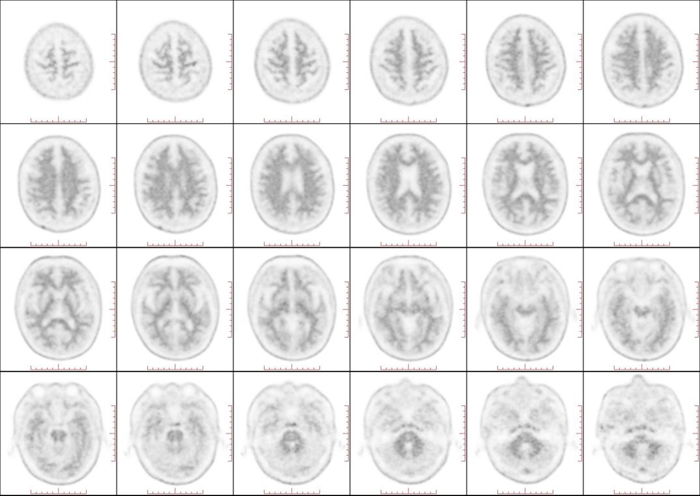

近日,一项旨在攻克阿尔茨海默病(AD)诊断难题的尖端技术在北京天坛医院成功落地。北京天坛医院核医学科与神经内科紧密协作,成功为一名记忆力下降患者完成了淀粉样蛋白(Aβ)PET显像剂氟[18F]贝他苯注射液的检查。此项检查标志着医院在阿尔茨海默病的早期、精准、无创诊断方面迈出了关键一步。

脑内Aβ蛋白异常沉积是AD病理的核心始发事件,可在症状出现前15-20年被探测到,从而抓住疾病干预的“黄金期”,实现早诊早治。Aβ PET是一种新型的脑显像技术,因其可以显示Aβ在脑中的分布和量化沉积斑块的严重程度,在AD精准诊断中具有重要价值。Aβ PET检测用于AD诊断,获得《2024美国阿尔茨海默病学会(AA)诊断和分期标准修订版》、《2024 国际工作组(IWG)推荐:阿尔茨海默病临床-生物学架构》、《2018中国痴呆与认知障碍诊治指南》等权威指南一致推荐。

随着Aβ-PET显像剂进入临床应用,以及AD治疗已经迈入靶向Aβ单抗精准治疗的新阶段,大量患者迫切需要通过Aβ PET显像进行疾病确诊及后期疗效评估。氟[18F]贝他苯注射液是国内首个获批的Aβ PET显像剂,为实现国内AD的早期、精准、无创诊断,提供了有利“武器”。北京天坛医院核医学科发挥自身的专业优势,积极参与 Aβ PET 技术的临床研究和应用推广,以期在疾病早期,当患者症状尚不明显时,及时准确地做出诊断,为患者赢得宝贵的治疗时间。